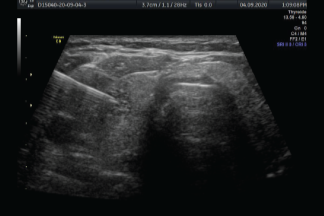

Una biopsia guiada por ultrasonido utiliza ondas sonoras para ayudar a localizar un bulto o anormalidad y extraer una muestra de tejido para examinarla bajo microscopio. Es menos invasiva que la biopsia quirúrgica, deja poco o nada de cicatriz, y no requiere de la exposición a la radiación ionizante.

La biopsia guiada por imágenes se realiza tomando muestras de una anomalía bajo alguna forma de guía, como ultrasonido, resonancia magnética o guía mamográfica.

Las imágenes por ultrasonido se utilizan para ayudar a guiar los instrumentos del radiólogo hasta el sitio del crecimiento anormal.